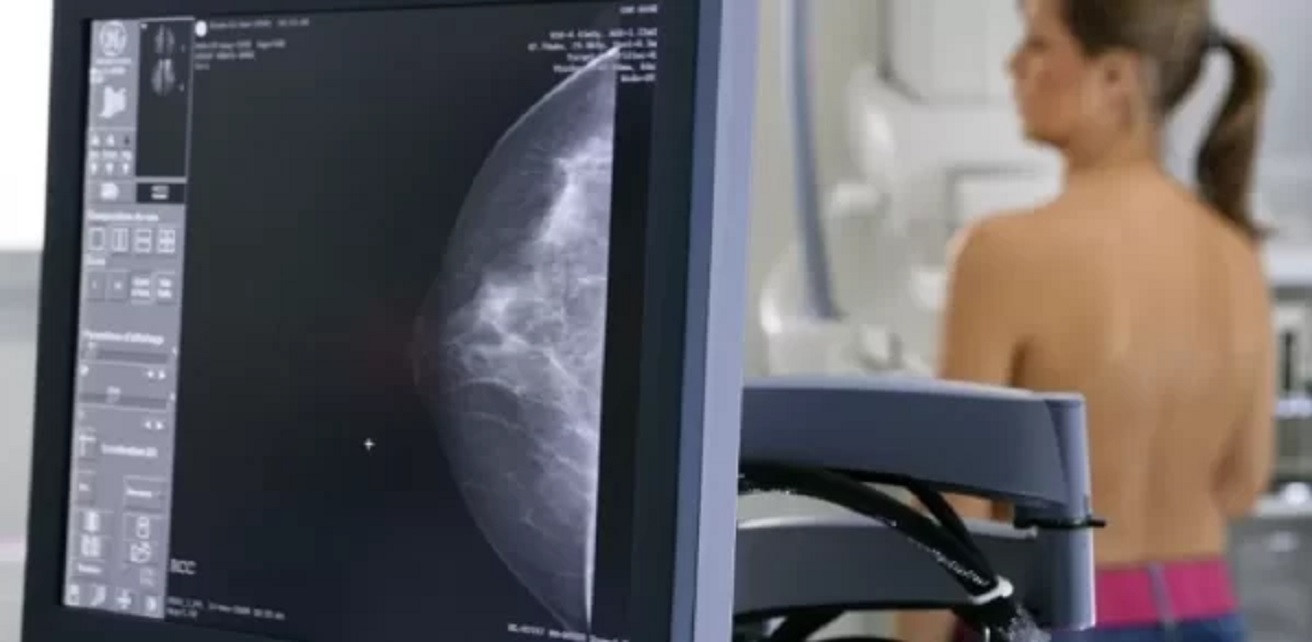

Ce investigaţii trebuie făcute, în funcţie de vârstă, pentru depistarea precoce a cancerului la sân

Medicul Isabela Maria Botea, specialist în radiologie-imagistică medicală, a explicat ce investigaţii trebuie făcute, în funcţie de vârstă, pentru depistarea precoce a cancerului la sân. Ea a arătat că RMN-ul trebuie indicat de către medicul imagist-senolog în anumite situaţii, în care sunt anumite discrepanţe între ecografie şi mamografie.

„Ecografia se poate face oricând, o dată pe an. În anumite situaţii se face la şase luni, nu mai devreme. Nu s-a demonstrat că, dacă faci ecografie în trei luni, se întâmplă ceva pozitiv, din contră, trebuie să laşi lucrurile, să poţi să faci un control corect, să vezi evoluţia. În ceea ce priveşte mamografia, care este singura metodă de screening pentru cancerul de sân, se face după vârsta de 40 de ani sau începând cu vârsta de 40 de ani, din doi în doi ani. În anumite situaţii se face şi mai devreme de 40 de ani sau se face mai des de doi ani. Se face la un an sau chiar uneori şi la şase luni, dar astea sunt situaţii particulare. RMN-ul nu se face de rutină, nu începem prin screening cu RMN, ci trebuie indicat de către medicul imagist-senolog în anumite situaţii în care sunt anumite discrepanţe între ecografie şi mamografie sau vedem foarte multe leziuni sau are un risc în familie de doamna respectivă şi vrem să clarificăm anumite aspecte”, a completat Isabela Maria Botea.

Potrivit acesteia, mamografia trebuie interpretată de un medic radiolog, evident, iar ecografia mamară este făcută de orice medic care are competenţă pe ecografie generală.